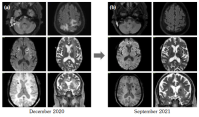

A 60-year-old female patient presented with subacute ataxic-hemiparesis progressing over two months. In the past, she was diagnosed with end-stage renal disease, with anti PR3 antibodies, and was receiving maintenance hemodialysis for 2.5 years. One year earlier, she presented with a mass in the right breast; histopathology had demonstrated non-caseating granulomas with no evidence of mycobacterial or fungal infection, and had responded to oral corticosteroids. On admission, magnetic resonance imaging (MRI) (Figure 1) showed multiple supra- and infratentorial brain lesions with perilesional edema (Figure 1a). Most lesions revealed a ‘target appearance’ on T2-weighted images with peripheral iso/hypointense rims surrounding the hyperintense central area. These were diffusion restricted centrally, and blooming in lesion wall on susceptibility images, all suggesting intracranial granulomas. Toxoplasma and tuberculosis serology (IGRA) were negative, but anti PR3-ANCA levels (EIA) were raised. The patient refused an invasive biopsy. The granulomas were considered a part of the granulomatosis with polyangiitis (GPA) and an oral steroid trial showed a marked improvement in the ataxia and weakness. Rituximab was administered. Control MRI documented reduction in size and perilesional edema (Figure 1b). Intracranial manifestations of GPA, apart from those attributed to vasculitis, are granulomas that are usually contiguous with extracranial sites such as sinuses or the mastoid.[1] This patient had unusual remote granulomatous disease in two distinct organs: the breast and brain.